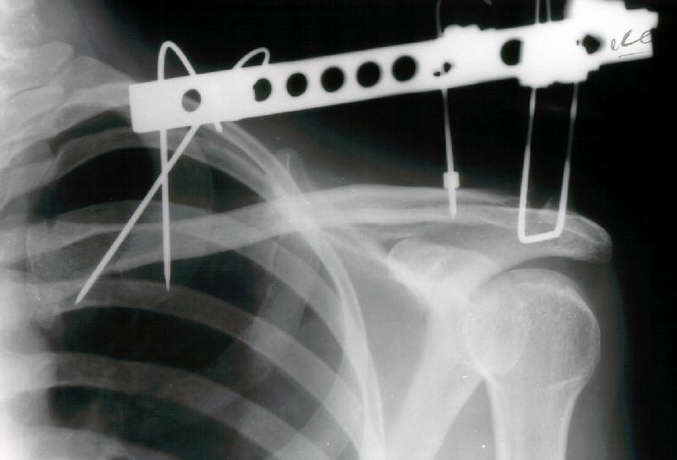

Since we have no experience with external fixation of the clavicle, we did not use this method. However, it is very interesting to see. We elected to use a T plate with a screw into the coracoid as shown in the X-ray below.

AM>We elected to use a T plate with a screw. Any comments would be appreciated.